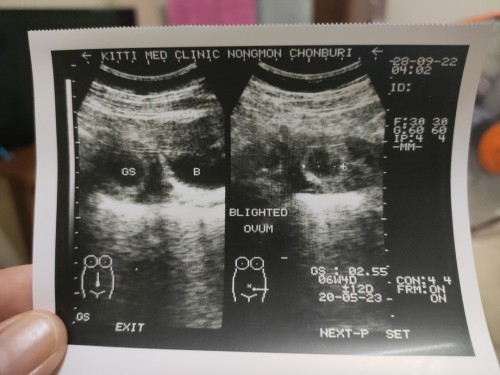

ท้อง 7 สัปดาห์ 2 วัน

วันนี้ไปซาวด์ดูน้อง เนื่องจากมีเลือดออกเป็นน้ำสีตาล เเล้วหายไป พอไปซาวด์ดูน้องปรากฏว่า มีเเต่ถุงการตั้งครรภ์ไม่มีตัวอ่อน ( ซาวด์ผ่านหน้าท้องค่ะ )หมอสันนิษฐานว่า จะท้องลม เราใจไม่ดีเลย วันที่ 12 ตุลาคมนัดซาวด์อีกรอบ เราควรเปลี่ยนคลินิกซาวด์มั้ยคะ???